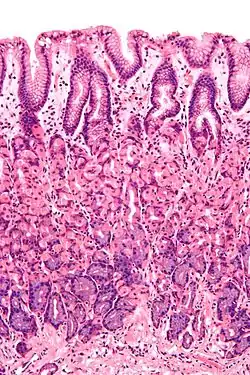

Histological section taken from the gastric antrum, showing the mucosa of the stomach | |

The mucosa is composed of one or more layers of epithelial cells that secrete mucus, and an underlying lamina propria of loose connective tissue.[1] The type of cells and type of mucus secreted vary from organ to organ and each can differ along a given tract.[2][3]